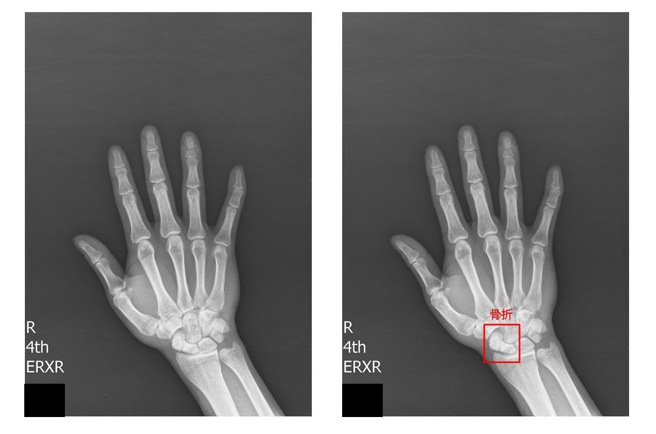

腕部舟状骨骨折软体侦测,医疗影像输入(图左)由软体标示出异常骨折(图右)处,俱备即时提示骨折处。( 图/ 长庚医院提供)